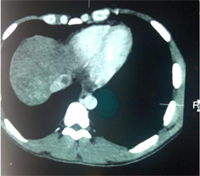

Abdominal ultrasonography showed a homogenous dysmorphic hepatomegaly with a hypertrophic caudate lobe, a splenomegaly and a mild ascites (Figure 1). Right and middle hepatic veins were obstructed. The left hepatic vein was permeable and dilated (Figure 2). We completed imaging with an abdominal computed tomodensitometry (Figure 3) with contrast enhancement. We observed the same aspect of hepatomegaly with an enlarged caudate lobe, splenomegaly and mild ascites. Moreover, the right hepatic vein was hyperechoic suggesting an obstructive thrombosis. The middle hepatic vein was also hyperechoic and partially obstructed. The left hepatic vein and the inferior vena cava were normal. These

Figure 3. Abdominal computed tomography of November 2022 showing a thrombosis of the middle hepatic vein.

thrombosis aspect of right and middle hepatic vein suggest a BCS. We didn’t do an abdominal Magnetic Resonance Imaging (MRI). We didn’t assess liver stiffness due to the presence of ascites. We didn’t deliver biopsy via the trans jugular route as it is unavailable in our setting. Gastroscopy showed grade 1 esophageal varices and a moderate portal hypertensive gastropathy.